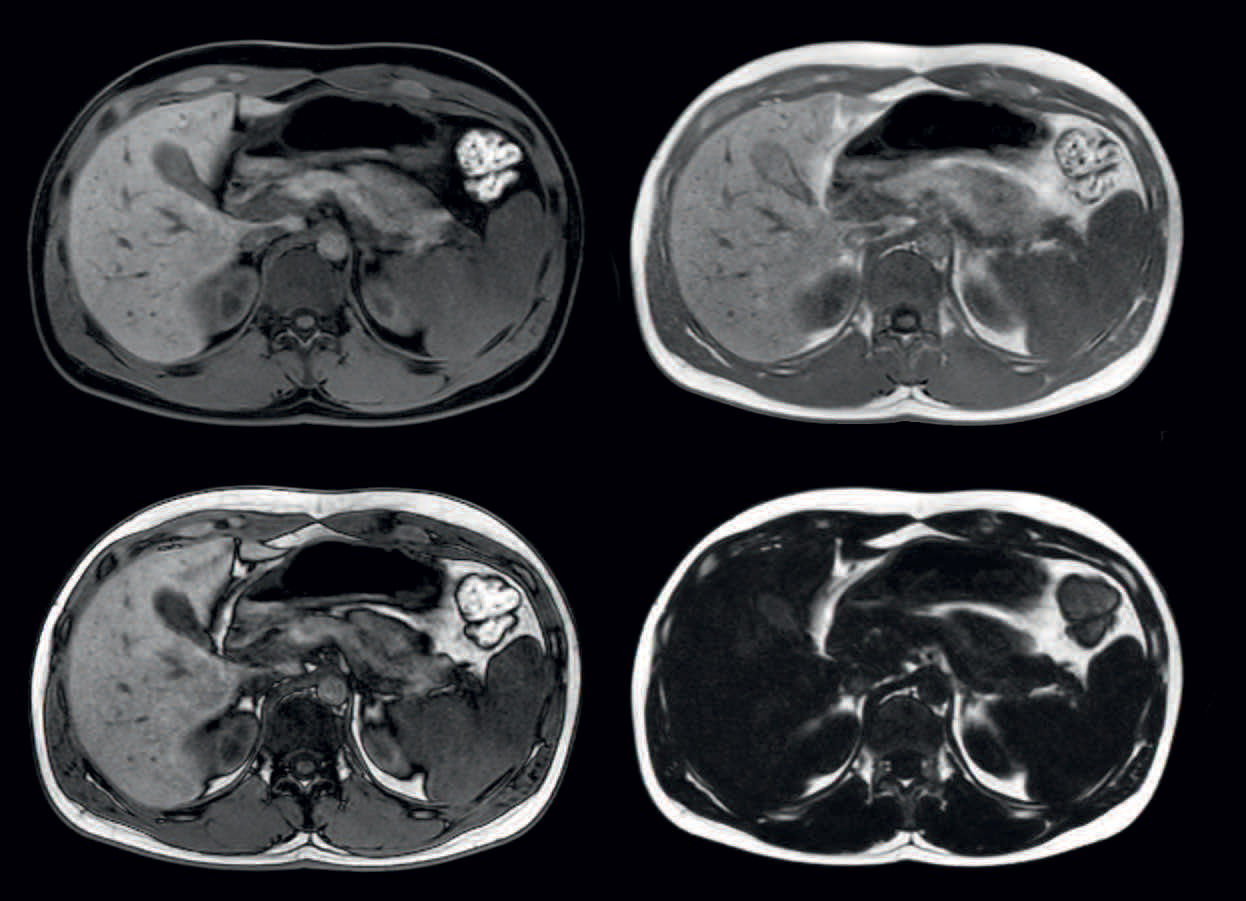

Four different contrasts in one breathhold

mDIXON provides four different contrasts in one scan: water, fat, in-phase and out-phase images. Voxels 1.3 x 1.5 x 2.5 mm, high dS SENSE acceleration factor, breathhold 16 seconds.